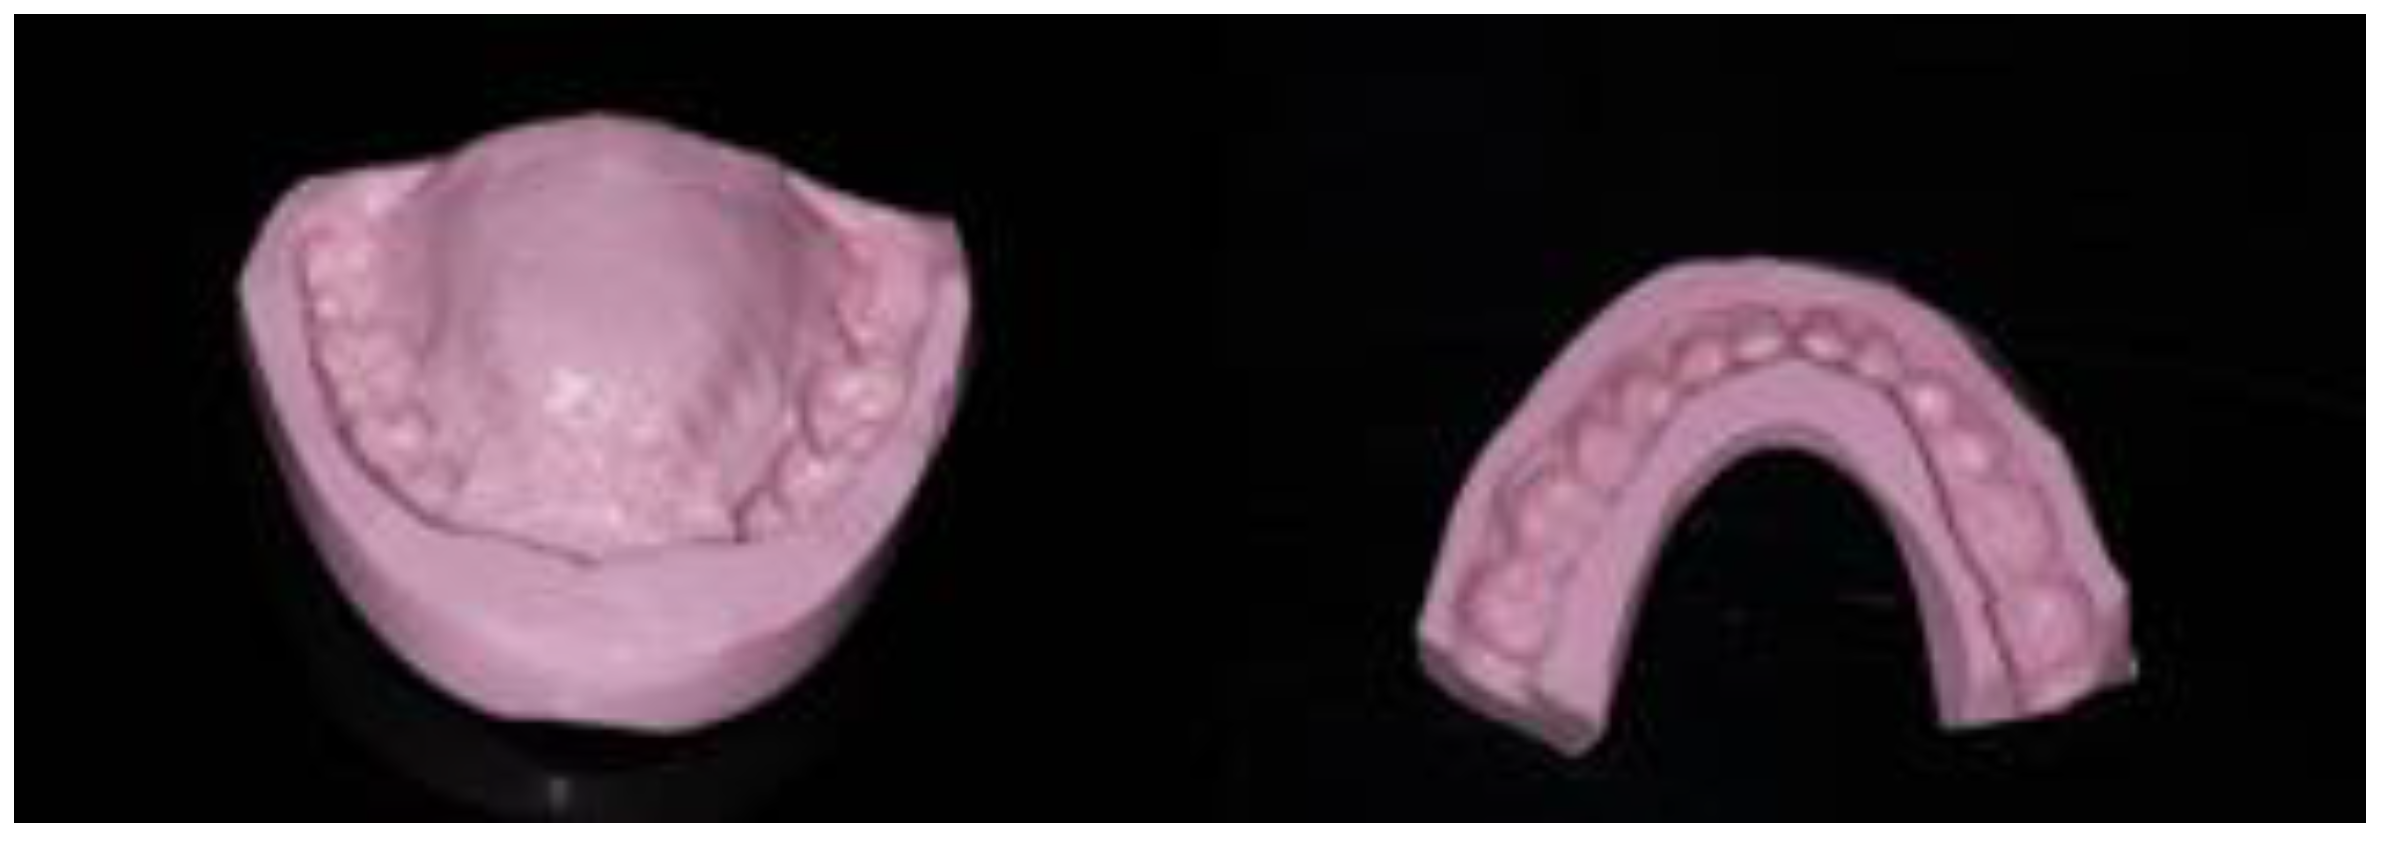

The centric relation was defined as a reference position to increase the vertical dimension of occlusion. It was recorded using an anterior deprogramming device (Lucia Jig technique), and then a silicone occlusion was placed posteriorly. The initial study casts were mounted at the new vertical dimension of occlusion (VDO) on a semi-adjustable articulator (SAM, semi-adjustable) using a facebow transfer for the maxillary and with the registration in centric relation for the mandible (Figure 4). The diagnostic wax-up was completed in accordance with the clinical findings.

Placement in articulator of the models using the Lucia Jig and an occlusal bite (a,b) and wax-up of the models in the new vertical dimension of occlusion (c,d).